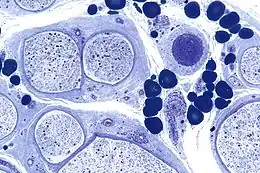

Description de cette image, également commentée ci-après

Coupe histologique révélant une neuropathie périphérique secondaire à une vascularite. Coloration au bleu de toluidine. Fixation époxy.